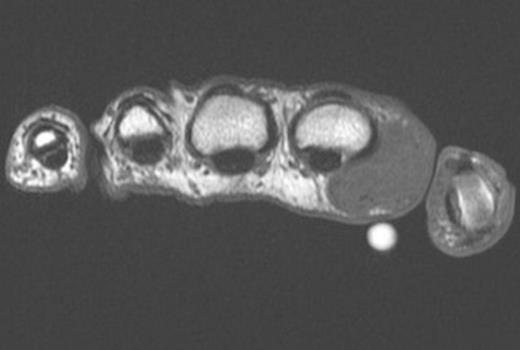

Axial T1 weighted MRI image of the mass and overlying marker (volar white circle)

Ultrasound scan prior to referral suggested a complex mass with solid and cystic components. MRI scan demonstrated (Figure 1 and 2) the mass to be mixed fibrous and cystic components reported by a radiologist to be either fibromatosis or a desmoid tumour. The lesion was closely positioned to the Metacarpophalangeal joint but not invading the capsule. There was no sign of osteoarthritis of the joint. A marginal excisional biopsy was performed utilizing a Bruner incision. A firm fibrous mass was found with pale coloured tissue with cystic spaces containing ganglion like jelly. The mass easily reflected off the subcutaneous dermis but deep was intimately related to the palmar fascia. The radial digital nerve and vessels were separate to the mass and preserved. The wound healed well without complication. Histopathological analysis showed an irregular mass of fibrous tissue and pale mucoid material measuring 34 x 25 x 15 mm. There were multiple cystic areas containing mucoid material. (Figure 3)